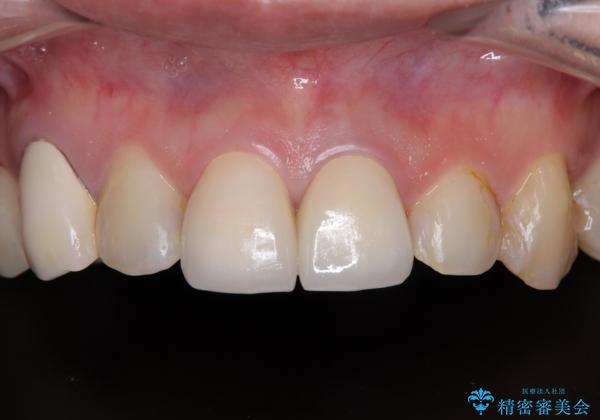

変色と捻れた前歯 オールセラミッククラウン補綴治療

- むし歯により神経を取り除く処置をした歯と隣接する歯の捻れを気にして来院された患者様です。

神経を取り除いた歯は変色が始まっており、隣の歯は捻れにより突出している印象であったので、前歯2歯をオールセラミッククラウンにて補綴することとしました。

神経が露出しないよう慎重に行った結果、神経を保存することができました。処置後に多少の痛みが生じましたが、その後は良好な状態が続いています。

色、形ともに、自然な仕上がりとなり、患者様には大変満足していただきました。